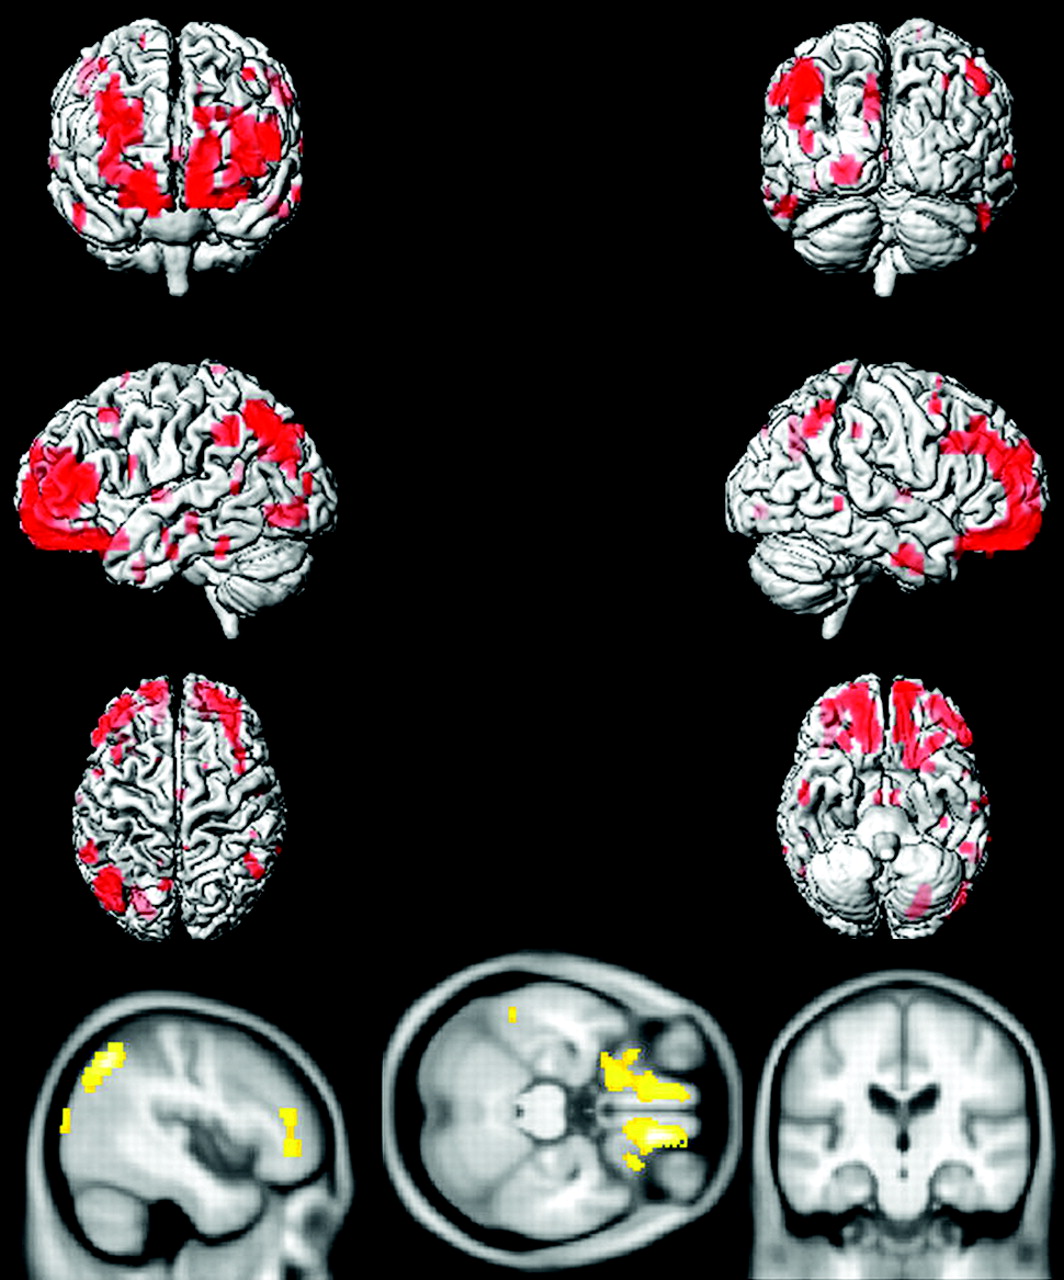

Voxel-based analysis by using SPM5 demonstrated that compared with age-matched CN subjects, aMCI-young patients had decreased glucose metabolism in the precuneus, posterior cingulate gyrus, medial temporal lobe, and lateral temporal and parietal lobes in both hemispheres, consistent with the typical pattern of FDG-PET changes observed in AD (Fig 3). The regional decrease in FDG uptake in aMCI-old patients compared with age-matched CN subjects, however, was different from the AD-like pattern observed in aMCI-young subjects, primarily involving the orbitofrontal and prefrontal cortices in both hemispheres and the left lateral parietal lobe (Fig 4).

Voxel-based analysis of the FDG-PET uptake-to-pons ratio in aMCI-young patients compared with age- and sex-matched CN-young subjects (P < .005 uncorrected).

Voxel-based analysis of the FDG-PET uptake-to-pons ratio in aMCI-old patients compared with age- and sex-matched CN-old subjects (P < .005 uncorrected).

The pattern of gray matter atrophy in aMCI-young patients mirrored the pattern of reduction in glucose metabolism in this group, involving mainly the precuneus, medial temporal lobe, and lateral temporal and parietal lobes in both hemispheres and some involvement of the prefrontal cortex (Fig 5). On the other hand, the cortical atrophy was far less significant in aMCI-old subjects mainly involving the hippocampus and the basal forebrain in both hemispheres, and a few clusters were present in the prefrontal cortices (Fig 6).

Pattern of gray matter reduction in aMCI-young patients compared with age- and sex-matched CN-young subjects demonstrated in red and yellow (P < .005 uncorrected).

Pattern of gray matter reduction in aMCI-old patients compared with age- and sex-matched CN-old subjects demonstrated in red and yellow (P < .005 uncorrected).